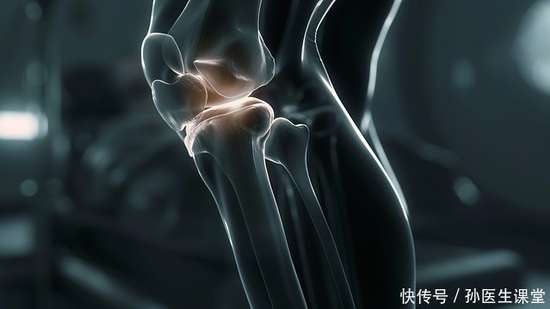

检查后,医生的话让她愣住了:“这是骨关节炎的早期表现。”她不解:“这不是老年病吗?”医生轻轻指着关节模型解释:“关节软骨就像齿轮间的润滑垫片,年轻时会自我修复,但一些习惯会让磨损提前发生。”

第三个习惯,是“忽视身体的预警信号”。 其实她的膝盖在一年前就有过偶尔的酸胀感,尤其在长时间行走或登山后,但她总以为是“累了,休息就好”。医生解释说,关节的疼痛、僵硬、活动时发出细微声响,都是身体在发出提醒。就像老房子门轴转动时的“吱呀”声,那是需要关注的信号。不少人常待关节出现肿痛、活动受限之状才前往就医,殊不知此时软骨磨损或许已较为显著,延误了早发现早治疗的时机,健康意识亟待提升。在病症早期给予关注并实施干预措施,通常能够更为有效地维系关节的正常功能,为机体的健康提供有力保障。